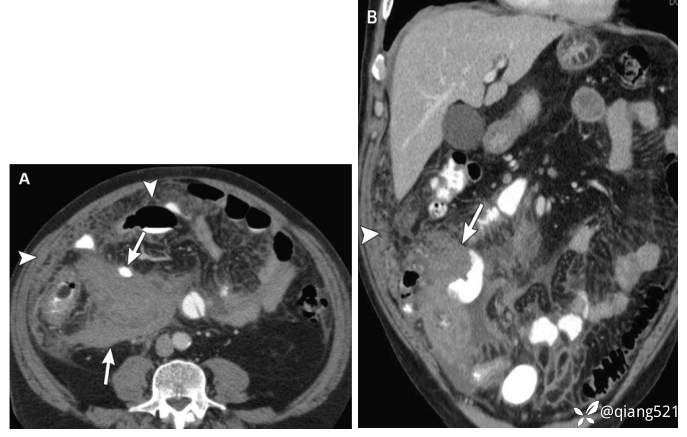

一名89岁的男性,患有转移性类癌。

横断上腹部(A)和中腹(B)的CECT显示右下象限不均匀强化的肿块(B中的箭头),右肝有一个微小的富血管病变,可能是转移性病变(A中的箭头)。患者血清5-HIAA水平升高。~(111)C-奥曲肽核素扫描显示肠系膜肿块有浓集的放射性示踪剂